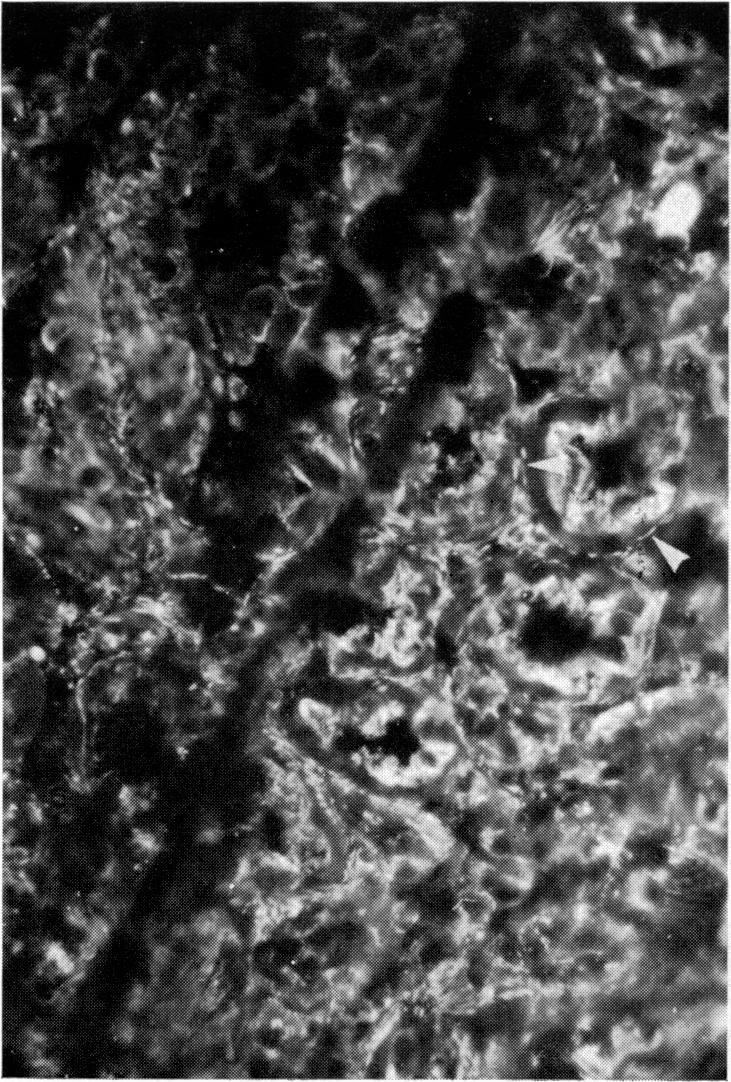

实验性平滑肌抗体。

Experimental smooth muscle antibodies.

Attempts were made to induce smooth muscle antibody (SMA) in rats by various procedures causing cell necrosis. Ligation of a liver lobe and cryosurgical damage to a liver lobe both resulted in subsequent appearance of SMA, provided the damage tissue was not removed. Transfer of the damaged liver tissue to the peritoneal cavity of a normal rat did not result in SMA production in the recipient. The SMA produced showed anti-actin and anti-heavy meromyosin specificity. Damage induced by hepatotoxic agents failed to give rise to SMA.

摘要

人们尝试通过各种导致细胞坏死的方法在大鼠体内诱导产生平滑肌抗体(SMA)。肝叶结扎和肝叶冷冻手术损伤均导致随后出现SMA,前提是损伤组织未被移除。将受损肝组织转移至正常大鼠的腹腔并未导致受体产生SMA。所产生的SMA表现出抗肌动蛋白和抗重酶解肌球蛋白特异性。肝毒性药物诱导的损伤未能产生SMA。